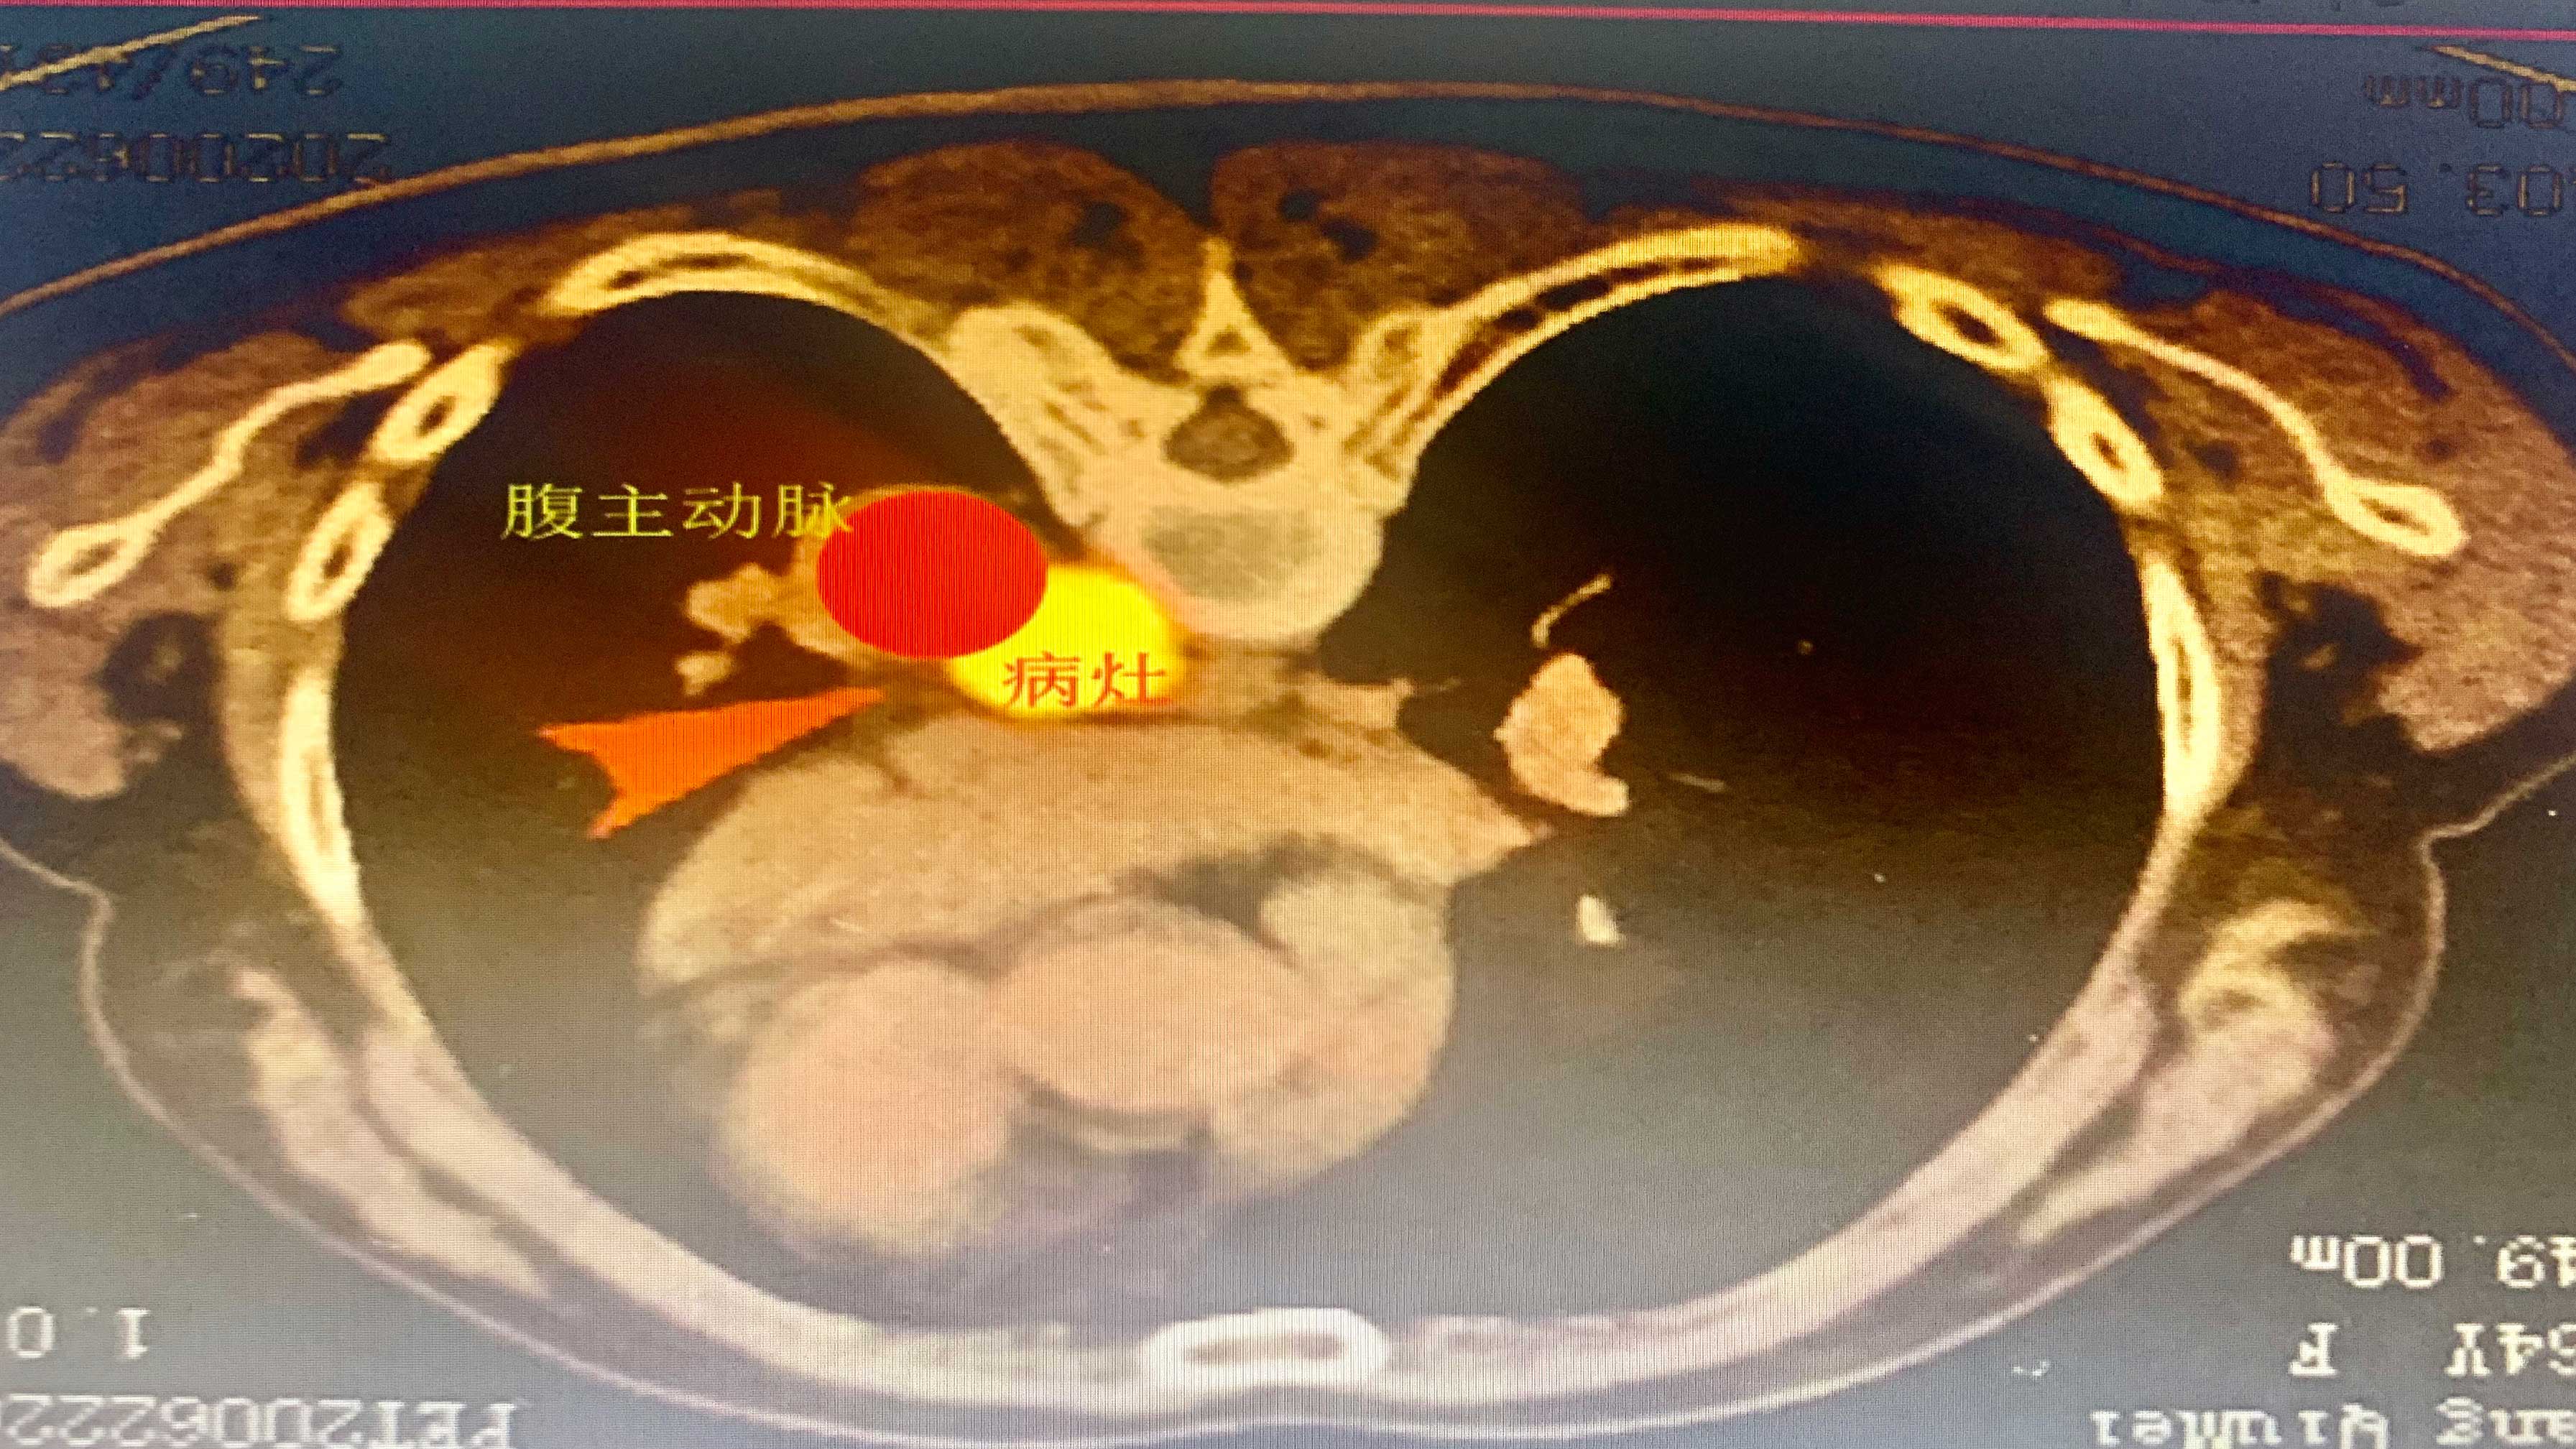

1、PETCT显示肿瘤的位置

穿刺的路径只有狭长细空间,稍有不慎粒子植入治疗过程中就有可能引起大出血危及患者生命。